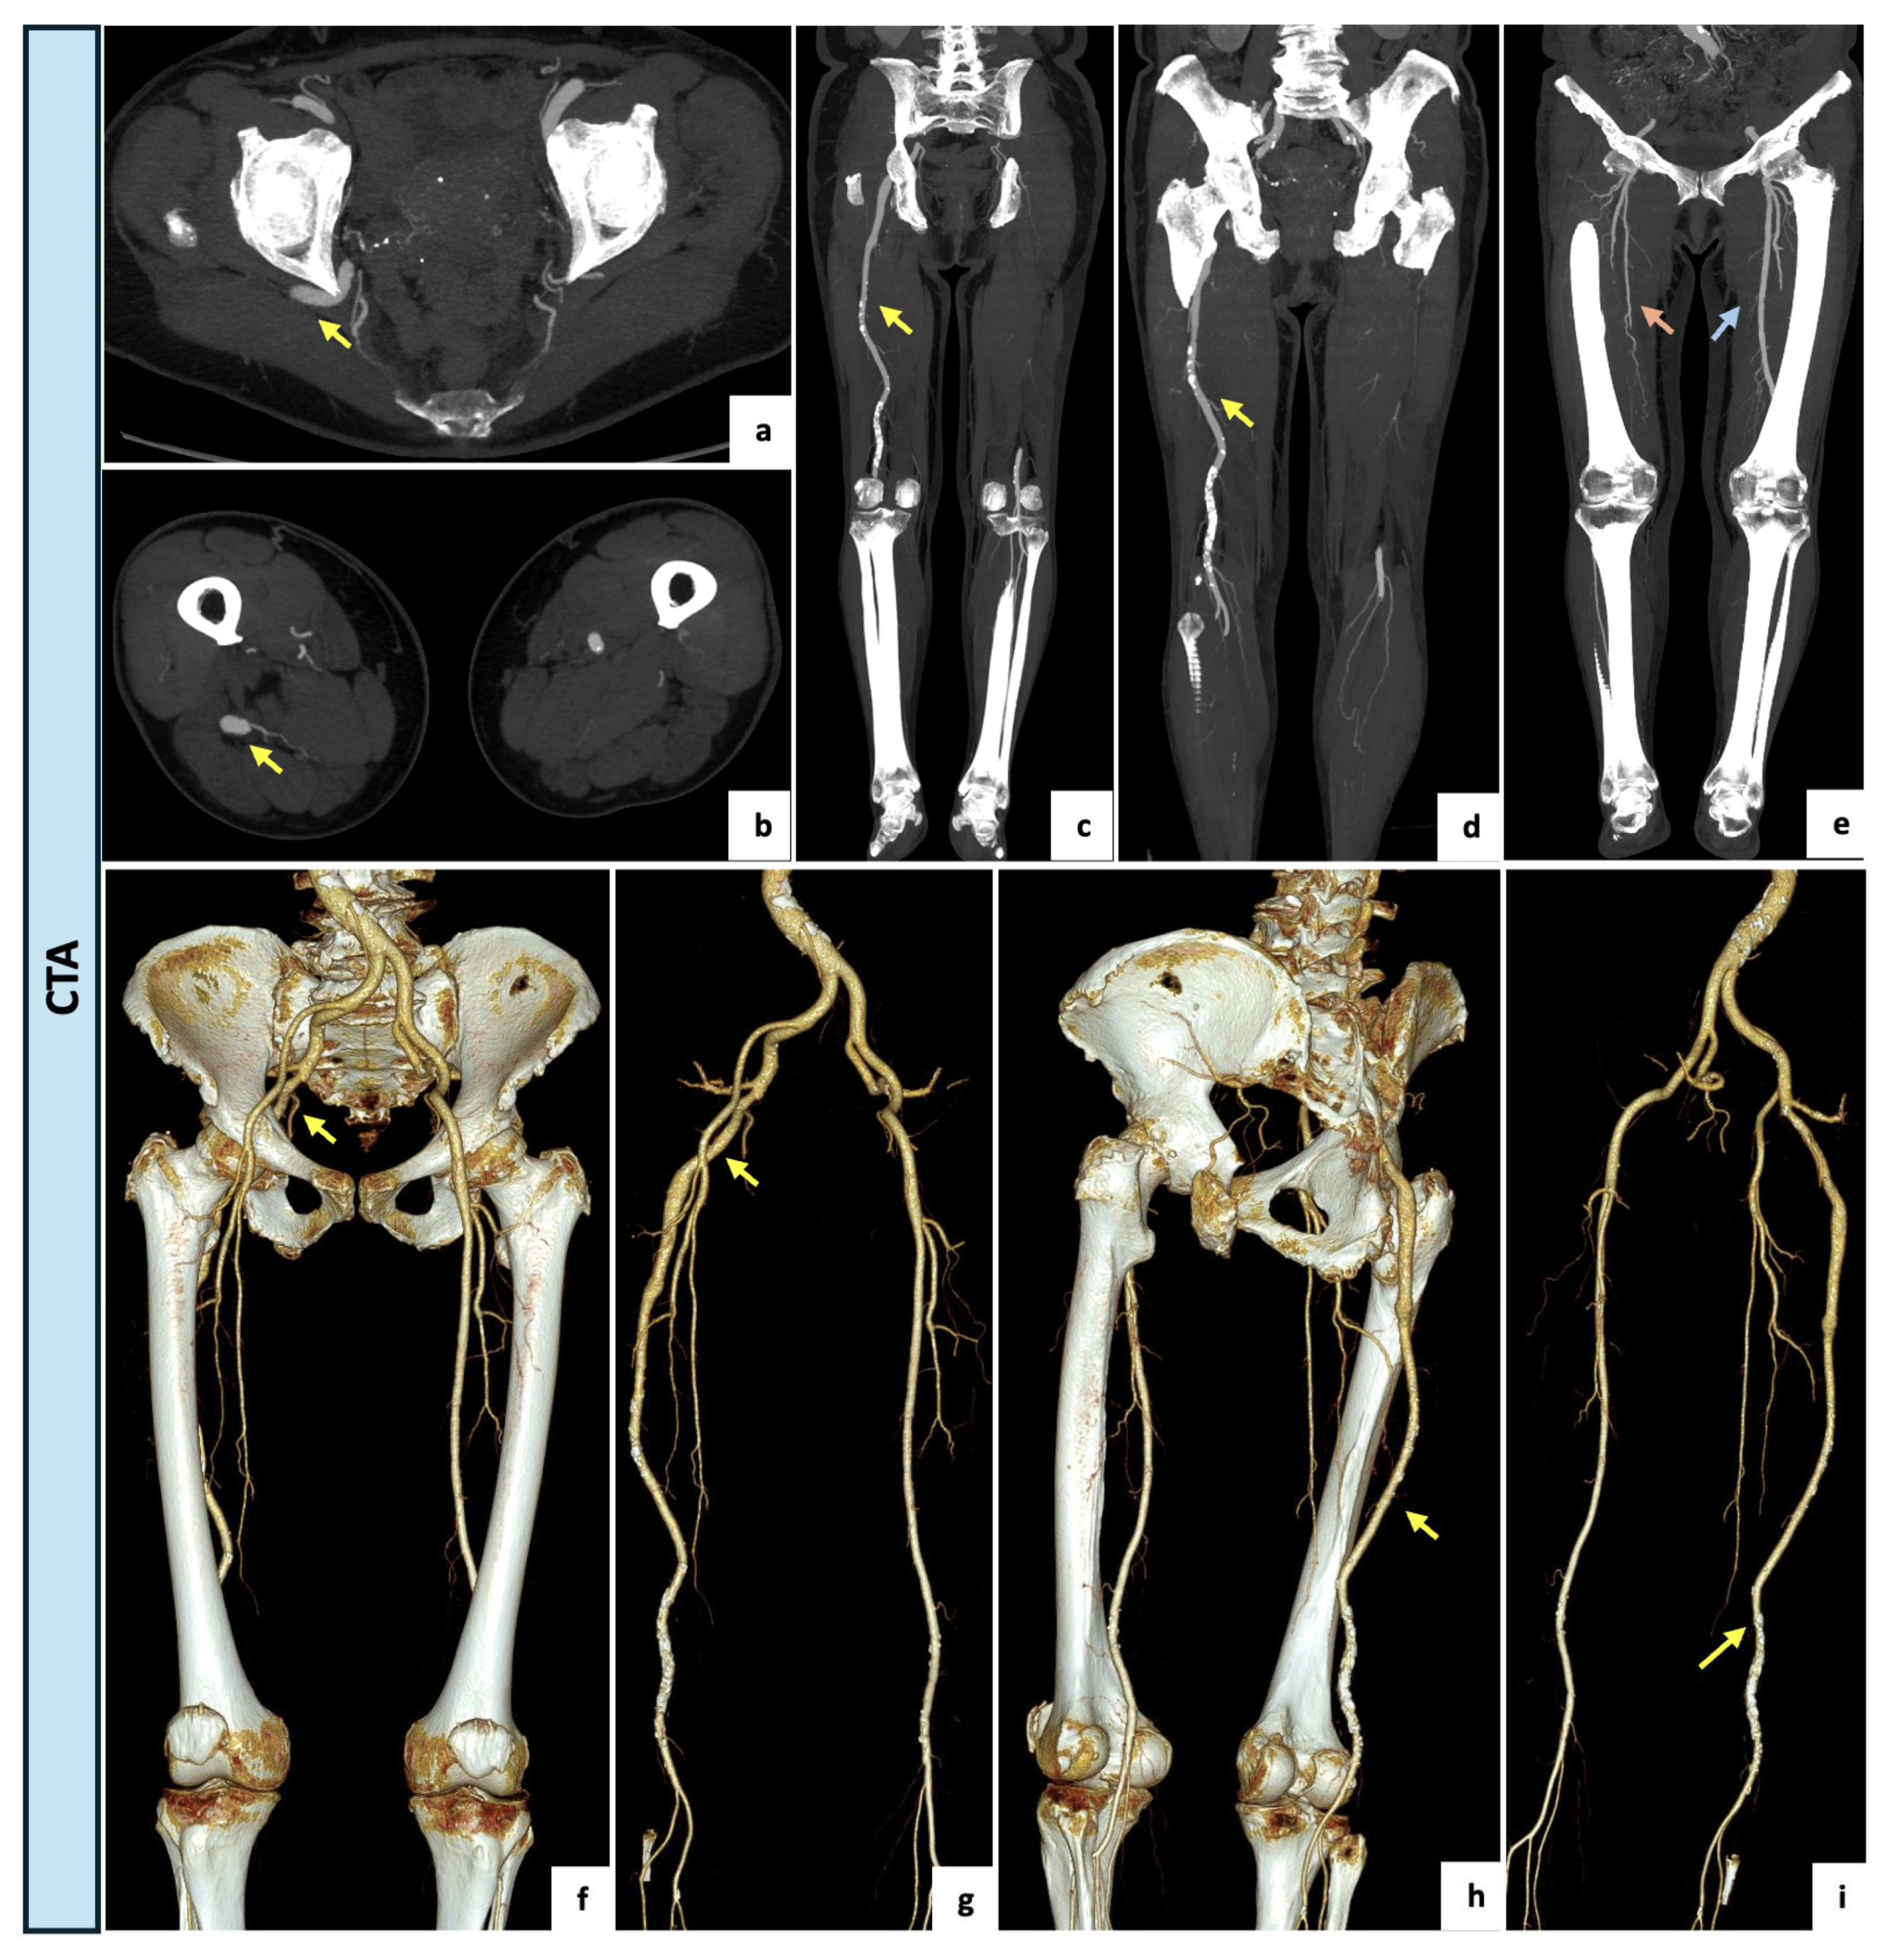

| 3 | 81 | Female | Moderate and recurrent back pain occasionally requiring pain medication | CTA | Right limb: Type 2a | Conservative management: single anti-platelet agent, analgesics. | Clinical FU: symptoms improvement with conservative therapy. No CTA FU needed. |

| 4 | 61 | Female | Type IIb bilateral claudication with left side worsening | CTA | Right limb: Type 1 Left limb: Type 2a | Medical management: smoke cessation, exercise training, glucose-lowering therapy, anti-platelet agents and cilostazol. | Clinical FU: progressive improvement. |